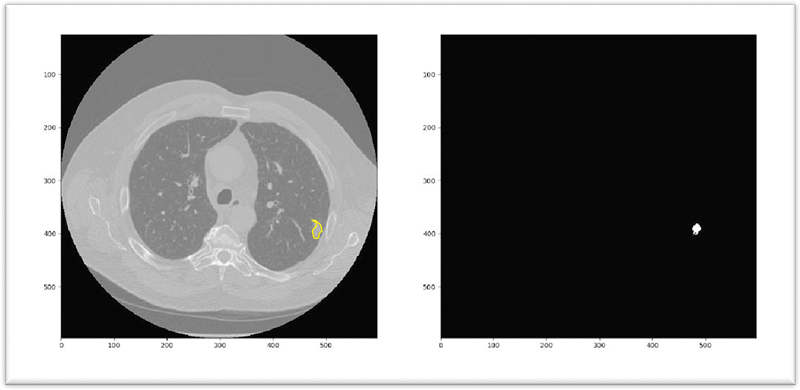

In this setting, AI aims to predict pixels/voxels of the nodule. The predictions can be used to do quantitative analysis of various clinical parameters of nodules, such as shape, volume, and distribution of pixel values ([Fig. 2]).

| Figure 2: Pulmonary nodule segmentation: an irregular solid nodule is segmented in the left lung highlighted in yellow.